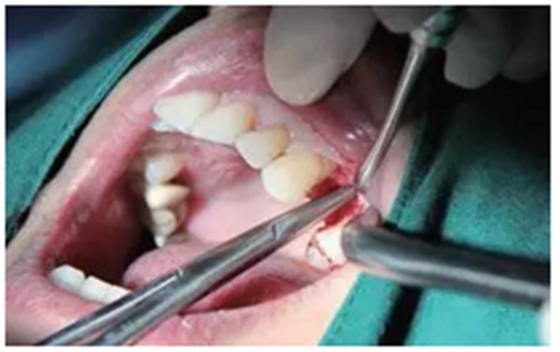

翻瓣與植入種植體

注意翻瓣不能太大,只需將窩洞頂端及周邊充分暴露即可。檢查種植窩洞頂端邊緣的骨壁情況,將窩洞頂端的高點(diǎn)去除,防止其干涉愈合基臺的就位。植入種植體植入時(shí)通過扭力扳手來確定最終的植入扭力,并判斷是否合適放置愈合基臺,也可以通過松動度測量儀測量ISQ值來判斷。

圖4 小翻瓣暴露窩洞頂端并去除高點(diǎn)